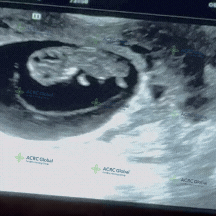

爱妈J的B超检查顺利完成,9周多的小宝宝虽然还很小,胎动还感觉不到,但在B超画面里已经能看到他灵动地滑动四肢,仿佛在和大家打招呼呢!小小的身影,健康有力的心跳172BPM!在场的爱妈看到这一幕,感动不已,直呼宝宝太可爱了!她迫不及待地将视频分享给准妈妈,让她也能感受到这个温馨又美好的时刻,期待宝宝继续茁壮成长!